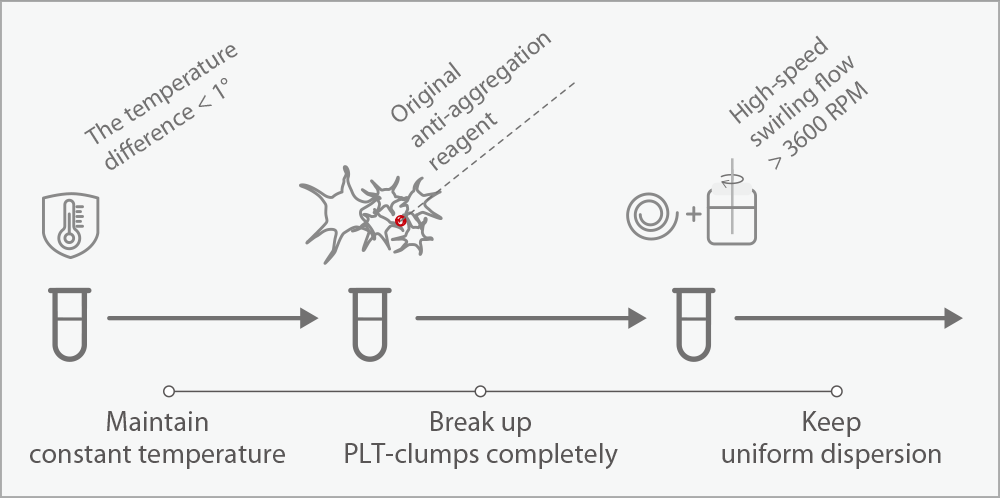

PLT-O with automated PLT-clumps de-aggreation technology

It solves the problem of falsely low PLT count samples caused by EDTA induced pseudo-thrombocytopenia.

Automatic retraction and re-testing with PLT-O